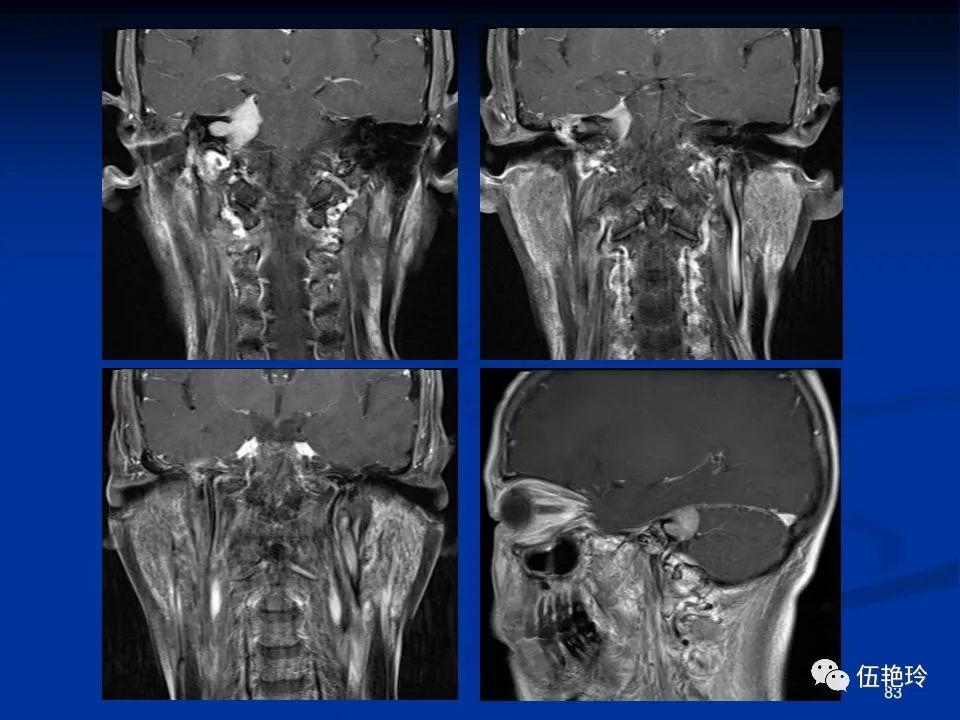

耳与面神经的解剖